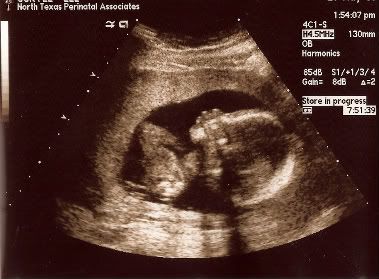

终于等到这一天,不知道是真的那么紧张跟期待,我前一晚竟然失眠了!一直摸着肚子 ,跟宝宝说"宝贝,明天要把脚打开开哦!让爸爸妈妈看看你是小王子还是小公主,那爸爸妈妈就可以正式开始买东西给你了!"

好不容易挨到12.30pm,老公回来接我去做ultrasound,今天的检查,是要看宝宝脑部,心脏等的发育。当然,还有要看宝宝的性别!我们是预约了1点的时间,可是哦,我们竟然等到快2pm才轮到我们!

好不容易盼到医生来了,她先看宝宝的心脏。。看了好几分钟,她突然停止所有动作,指着银幕,神色凝重的样子,当时我看了看老公,眼泪要涌上来了,听着医生说"你看到宝宝心脏有几个白点吗?" 我强忍着泪水点了点头,不知道她要宣布什么坏消息。。。。她继续说"通常这些白点是表示宝宝有可能是唐式儿的征兆之一!可是有很多例子证明 这些白点常常可以在亚洲人/宝宝的心脏看到,可是不代表宝宝会是唐式儿。你的年龄层加上你上次来做的唐式儿检查,报告说你宝宝是唐式儿的机会微乎其微。所以别担心!只是不知道为什么这些白点就是会在亚洲人看到!"

我真的被她吓到了很多下!!

照了心脏,就轮到宝宝的脑,肾脏,脊椎,手脚,眼睛,鼻子,嘴巴。。宝宝动得很厉害!不直是手脚乱挥舞,宝宝是整个身体180度,360度地翻来翻去!连医生都讲"你这个小坏蛋,太好动了吧?"嗨。。有点担心我这个宝贝以后会不会是"过动儿"啊??

等了好久。。医生终于说," 看来我门是看到了B。。O。。。Y。!!!!"

我跟老公虽然没有性别的偏好,可是一听医生这么说,我当场"哈哈哈!"笑出来,因为我可以开始shopping咯!!!!!

然后医生就把银幕停格,让我们"欣赏"宝宝的"小小鸟"!

这一次产检,医生给了我们宝宝的"特写"scan..看到宝宝的头。。我看了又看,跟老公手"我觉得宝宝很象他爸爸哦!!"

宝宝今天19周大了!16.36cm长!